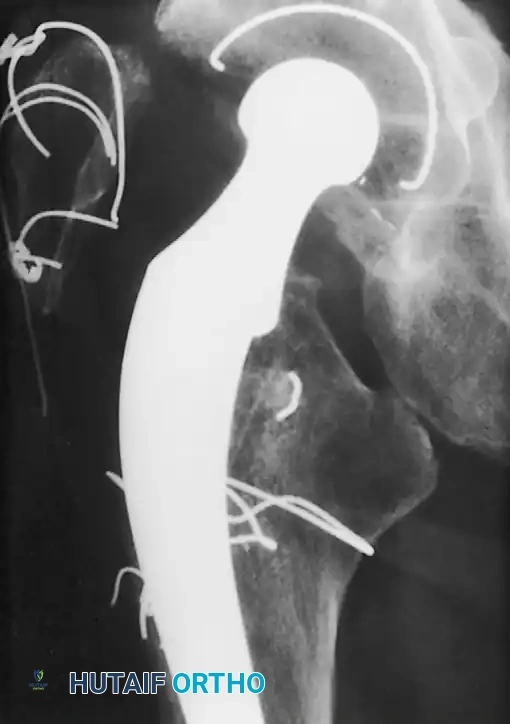

Associated Surgical & Radiographic Imaging